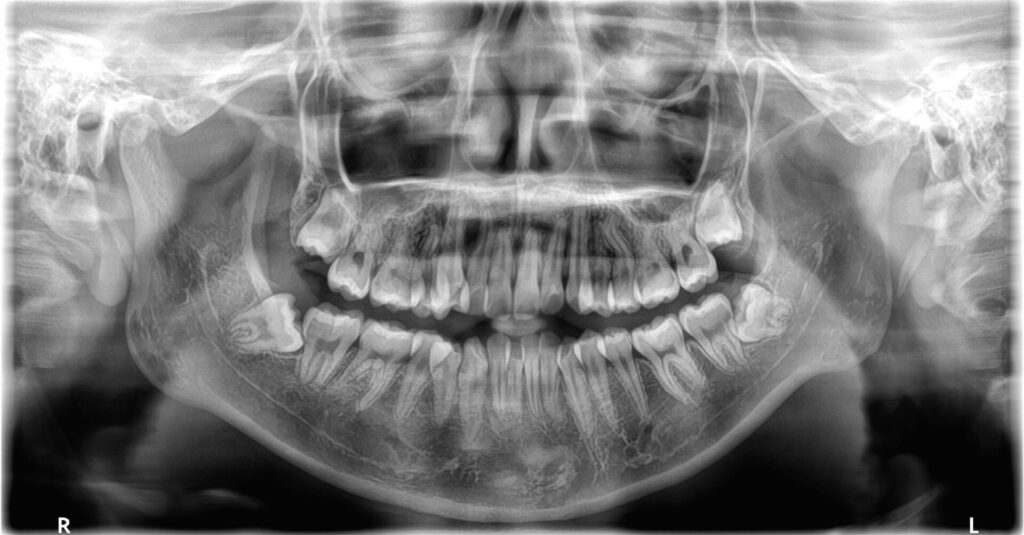

- パノラマレントゲン

スキャンによる歯列の確認やレントゲンなどを総合的に検査して矯正のプランニングをする準備をします